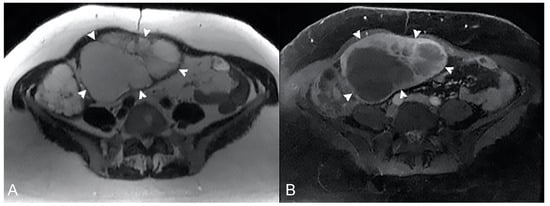

The infiltrative pattern is characterized by circumferential involvement of the wall, and it is responsible for different degrees of wall thickening and disappearing of the normal wall layers. Bowel wall infiltration looks like segmental and circumferential thickening, with homogeneous enhancement after gadolinium injection [33,34] (Figure 22).

Figure 22.

Example of Lymphoma in a 71-year-old male patient (the same patient in Figure 1C). (A) Axial T2-weighted image shows a marked asymmetric thickening of an ileal loop in the pelvis (arrows). (B) An axial T2-weighted image on a different plane shows multiple enlarged mesenteric lymph nodes (arrowheads).

The aneurysmal pattern often coexists with the infiltrative one and it can be its evolution. In this pattern, lymphomatous infiltration and disruption of the muscle layer and neural plexuses may be appreciated, resulting in loss of muscle tone and consequent bowel dilatation.